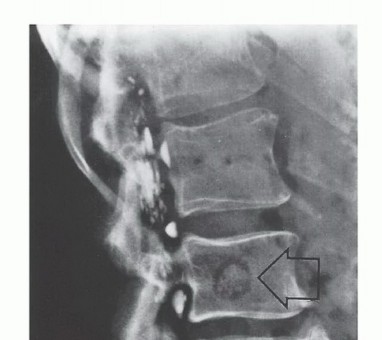

- Plain Radiography: The cornerstone of initial evaluation. It accurately predicts the diagnosis in over 80% of extremity bone tumors. It defines the lesion's location, zone of transition (narrow/sclerotic = benign/slow; wide/permeative = malignant/aggressive), cortical destruction, and periosteal reactions (Codman triangle, onion-skinning, sunburst pattern).

- Computed Tomography (CT): The modality of choice for assessing fine osseous detail, cortical integrity, and matrix mineralization. Thin-slice (≤1 mm) helical CT allows for precise 3D reconstructions. Intravenous contrast is essential to delineate the relationship of the soft tissue mass to major vascular bundles. Chest CT is mandatory for staging to rule out pulmonary metastases.

- Magnetic Resonance Imaging (MRI): The gold standard for evaluating the local extent of the tumor. It accurately defines the intramedullary extent (allowing calculation of bone resection levels), soft tissue extension, joint involvement, and the presence of skip metastases. T1-weighted images best define marrow replacement; T2-weighted and STIR sequences highlight peritumoral edema and the soft tissue mass. Contrast enhancement differentiates cystic from solid components and clarifies neurovascular proximity.

* Skip Metastases: Tumor nodules that have broken through the pseudocapsule and reside outside the reactive zone but remain within the same anatomic compartment. These represent locoregional micrometastases that have spread via local tissue planes or marrow sinusoids, independent of systemic circulation. The presence of skip metastases (seen in <5% of osteosarcomas preoperatively) is a dire prognostic sign and accounts for local recurrences when seemingly adequate margins are achieved without recognizing the skip lesion. Low-grade sarcomas may interdigitate into the reactive zone but rarely form true skip metastases.